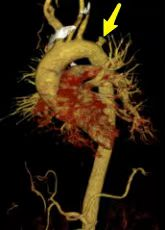

主动脉“修复”介入诊疗技术:

术前CT检查图: